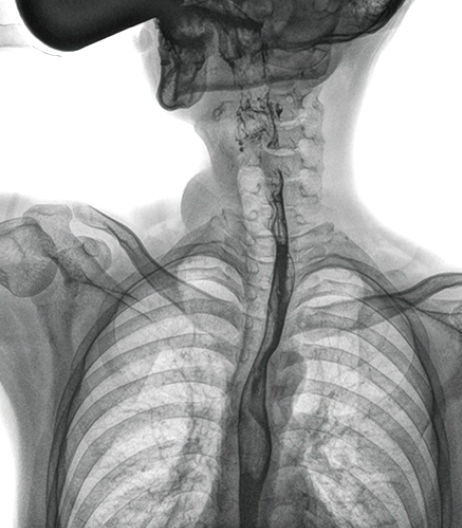

在食管造影檢查中,由于吞咽鋇劑后,造影劑流速非??欤瑒?dòng)態(tài)DR影像采集幅面大,普利德多功能動(dòng)態(tài)DR 17×17英寸超大視野,一次曝光即可顯示整個(gè)食管,更方便觀察食管的病變,確定病變的范圍,對(duì)診斷和治療有重要參考價(jià)值。

動(dòng)態(tài) DR 可以動(dòng)態(tài)觀察管壁蠕動(dòng)是否僵硬,以鑒別良、惡性狹窄,不但在透視過程中,可實(shí)時(shí)高清點(diǎn)片,實(shí)現(xiàn)毫秒級(jí)動(dòng)靜態(tài)圖像切換,快速捕捉病變部位的影像,成像清晰而迅速,盡可能減少食管功能性障礙患者因吞咽困難而忍受痛苦的時(shí)間,同時(shí)提高醫(yī)生做出正確診斷的效率,還能實(shí)時(shí)保存視頻影像,反復(fù)觀察、分析,明確病變范圍,對(duì)手術(shù)有重要的指導(dǎo)意義。

與過去的數(shù)字胃腸機(jī)比較,動(dòng)態(tài)DR圖像分辨率高,對(duì)食管的全景觀察,局部粘膜破壞、中斷,管腔狹窄以及病灶范圍的顯示清晰度明顯更優(yōu)。

上消化道造影高清圖像

由此不難看出,動(dòng)態(tài)DR在食管造影的臨床應(yīng)用上,相比于其他檢查手段,成像清晰、應(yīng)用便捷,而且能夠充分顯示食管的局部和整體結(jié)構(gòu)形態(tài),并以此揭示相關(guān)形態(tài)和功能性改變,更有利于助力實(shí)現(xiàn)精準(zhǔn)診斷。